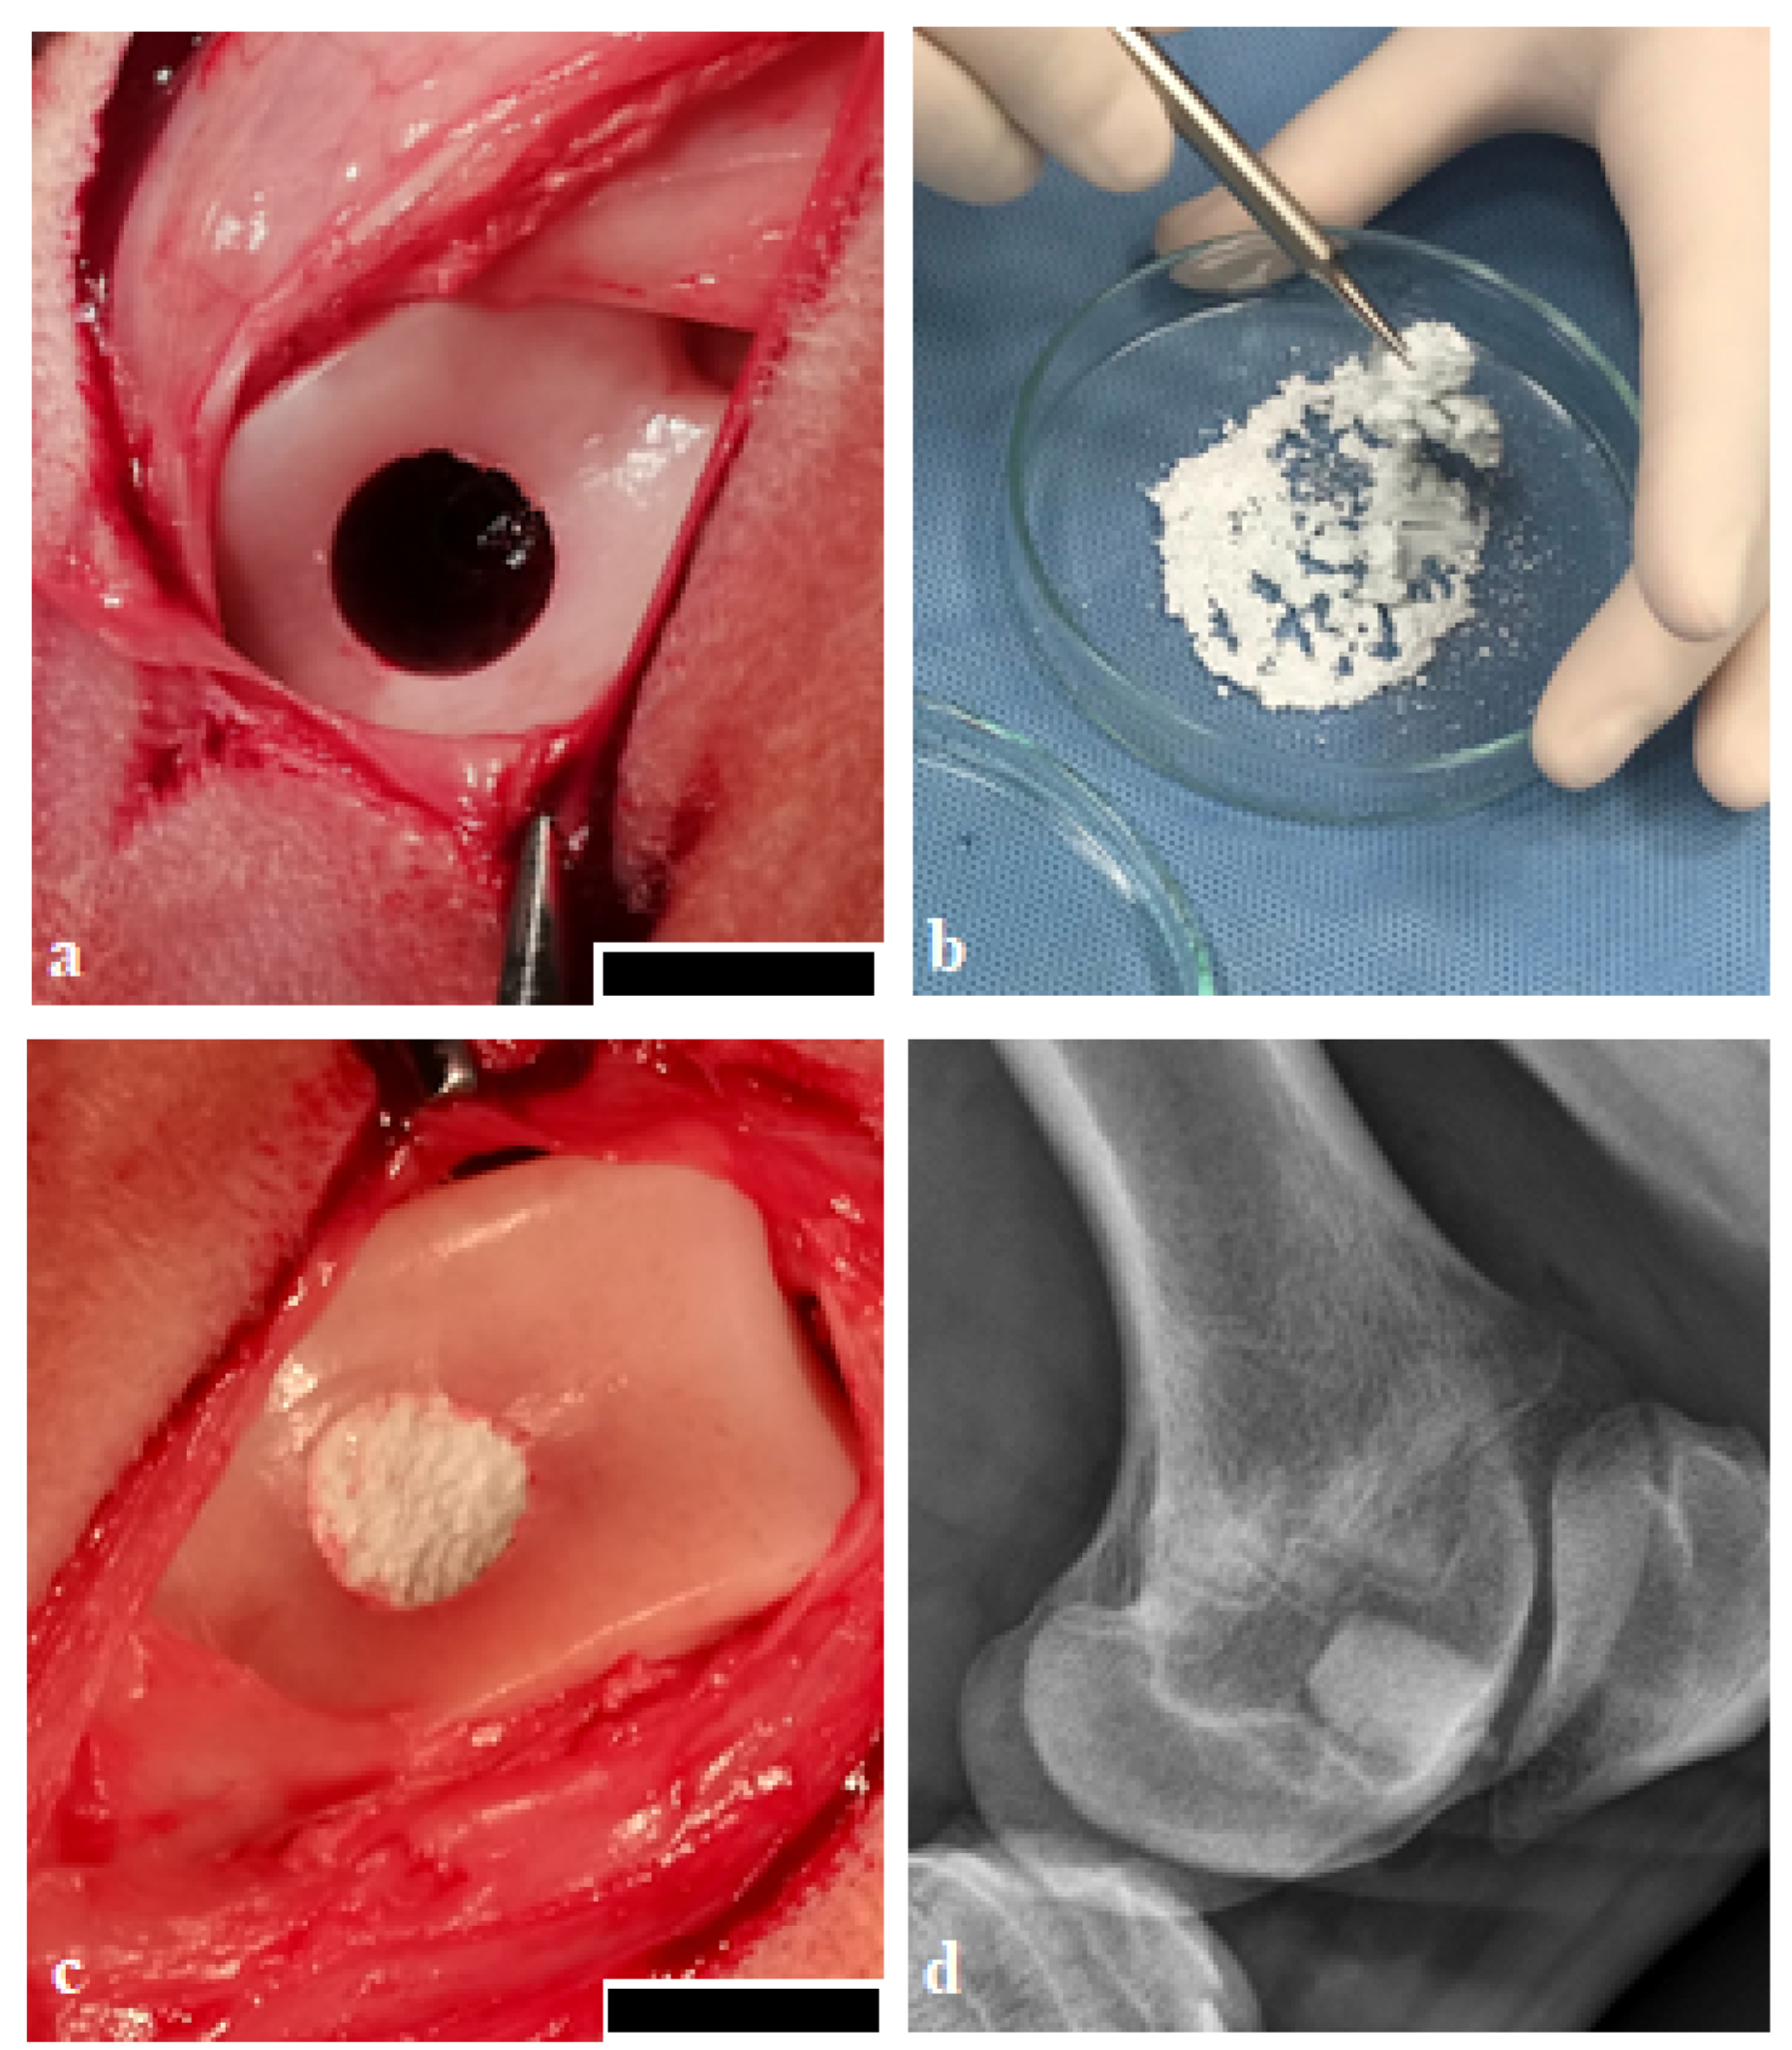

Figure 6.

Surgical procedure. (a) osteochondral defect of 8 mm diameter and 10 mm depth was created using an OATS kit in the trochlea ossis femoris, scale bar 1 cm, (b) preparation of the final biocement paste (biocement CX) before application to the osteochondral defect by mixing the powder and liquid components, (c) osteochondral defect after filling with biocement paste, scale bar 1 cm, and (d) X-ray confirmation after surgery.

In the case of enzymatically hardened CX biocement, the phytic acid (content 8 wt%) and phytase (Naturphos®, BASF, Ludwigshafen, Germany) were admixed to a liquid component. Phytic acid and phytase were separately dissolved in a solution of 0.5% acetic acid, and the enzyme reaction was in progress for 30 s. The final molar ratio of Ca/P (including phosphates from phytic acid) was 1.50. Hot-air sterilization at a temperature of 160 °C/90 min was used to sterilize the powder mixture. The final cement paste was prepared just before application to the osteochondral defect by mixing the powder mixtures with the liquid components (Figure 6).

All surgical procedures were performed under aseptic conditions. In general anaesthesia, the left hind limb of all animals was washed and shaved around the knee joint and prepared with a Betadine and alcohol solution using a sterile technique. A 10 cm-long surgical incision was made through the skin and soft tissue at the medial border of the patella. After luxation of the patella, the trochlea femoris was exposed. Osteochondral defects were created using a standard osteochondral autograft transfer system (OATS; Arthrex, Naples, FL, USA) 8 mm in diameter and 10 mm deep in the trochlea ossis femoris (Figure 6). Animals were divided into 3 groups. In group 1 (n = 6), osteochondral defects were treated with the biocement CX, in group 2 (n = 6) osteochondral defects were treated with the biocement C, and in group 3, untreated defects (n = 6) and empty defects were left to heal spontaneously. Control samples (n = 6) were taken from the healthy native cartilage obtained from extracted osteochondral cylinders. Immediately after filling the osteochondral defect, the skin and soft tissues were sutured, and the surgical wound was sprayed with an aluminium fluid spray. The absence of bone fractures, possible arthropathy, and the correct orientation of the osteochondral defects were confirmed by X-ray (Philips Digital Diagnost, Delft, The Netherlands) and the surgical wound was finally sprayed with aluminium spray.